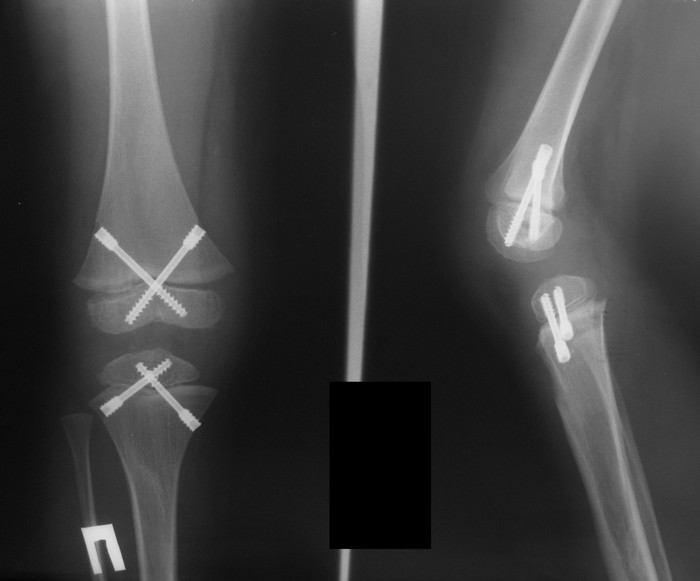

Ребёнок 4 года с подтверждённым диагнозом нейрофиброматоза и удлинением голени. Ребёнок 4 года с подтверждённым диагнозом нейрофиброматоза и удлинением голени. На настоящий момент имеется удлинение и увеличение в размерах правой голени и стопы относительно левой конечности до 5 см. Коррекция диспропорции ног стельками в связи со значительной величиной укорочения уже затруднительна, в связи с чем планируем оперативное лечение. Вопрос возник относительно того, что делать - удлинять здоровую конечность, либо укорачивать увеличенную? С одной стороны, укорочение технически проще, но имеет свои недостатки - слабость мышц вследствие укорочения. С другой стороны: удлинение здоровой конечности - длительный срок аппаратной дистракции и фиксации со всеми вытекающими, необходимость "лечить здоровую ногу"...Хотелось бы знать мение уважаемых коллег.Заранее спасибо.

Действительно хорошая идея сделать именно ВРЕМЕННЫЙ эпифизеодез с применением 8-образных пластин, установленных с двух сторон на проксимальную зону роста большеберцовой кости. До 1,5 лет их можно оставить без последствий для ростковой зоны. Применение винтов для блокирования ростковой зоны приведет к её закрытию, за чем последует значительное укорочение сегмента в связи с малым возрастом ребенка.

Почитал - действительно, у Кэмпбелла очень убедительно написано и нарисовано про блокирование зон б/б и бедренной костей 4 винтами. Про закрытие зоны роста ничего не сказано, наоборот, отмечается "обратимость" эпифизеодеза. Наверное, остановимся на этом варианте.

По поводу выбора screw vs 8-plate для эпифизеодеза ГОЛЕНИ:

Efficacy and late complications of percutaneous epiphysiodesis with transphyseal screws

http://www.boneandjoint.org.uk/highwire/filestream/46985/field_highwire_article_pdf/0/270.full.pdf

Взвесили все "за и против" и остановились на эпифизеодезе. Теперь будем ждать результатов.